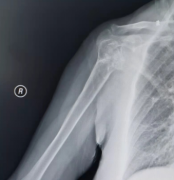

全膝关节置换术(膝关节退变性骨关节炎)

复杂全膝关节置换术(膝关节固定性髌骨脱位)

膝前内侧骨关节炎 (单髁置换术)